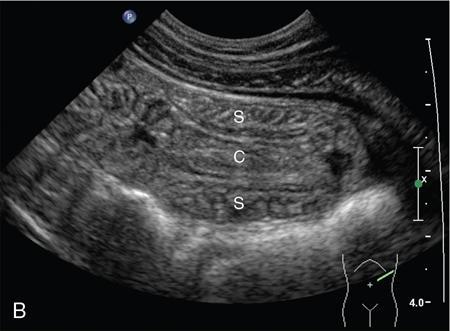

Ajay Taranath, Lino Piotto Intussusception is a common cause of acute abdominal pain in children. In this condition, a portion of the bowel wall, the intussusceptum, invaginates into the lumen of the portion of the bowel immediately distal to it, the intussuscipiens. It occurs most commonly in the first two years of life but is sometimes seen in older children. Once the invagination process has begun, the first part of the intussusceptum (the head) is pushed distally by peristalsis dragging the wall of the bowel with it. This tends to be progressive once it starts and as the invagination continues, interference with the blood supply of the intussusceptum causes venous occlusion and subsequent mucosal congestion. In advanced cases, the vascular compromise may result in the passage of blood-stained mucus through the rectum (red-currant jelly). Intussusception may be idiopathic or may be due to a pathologic ‘lead point’ such as a Meckel’s diverticulum, duplication cyst or neoplastic mass within the bowel wall. Most patients under the age of 2 years are in the idiopathic group. These are thought to be associated with thickening of bowel wall caused by hyperplasia of Peyer’s patches in response to a recent viral infection. Pathologic lead points are much more common in patients older than 4 years. For this reason, the head of the intussusceptum in these patients should be scanned carefully for evidence of a lead point. Intussusception is usually described according to the bowel that is involved. Those involving only small bowel include jejuno-jejunal (jejunum into jejunum) and ileo-ileal (ileum into ileum), are often seen as an incidental finding in abdominal sonography and only infrequently require intervention, when they have caused a bowel obstruction (Fig. 7.12.1A and B). Those involving large bowel include ileo-colic (ileum into colon), ileo-ileo-colic (ileum into ileum and then into colon) and colo-colic (colon into colon) and almost always require intervention. The most common of these is the ileo-colic type, in which the terminal ileum invaginates the colon through the ileo-caecal valve. The longer the intussusception persists, the greater the likelihood of gut necrosis and the need for surgical resection. Typically, children with intussusception will present with some or all of the following clinical features: attacks of colic, vomiting, blood and mucus per rectum, palpable abdominal mass. The attacks of colic are often associated with drawing-up of the legs. The duration of symptoms is usually less than 48 hours. The peak incidence is around 18 months though it can occur in children as young as 5 months and as old as 15 years. Traditionally, children suspected of suffering from an ileo-colic intussusception would be investigated with supine, erect and occasionally prone plain radiographs. When the clinical suspicion was high, the only way to confirm or exclude the presence of an intussusception was to perform a barium enema. A hydrostatic reduction using barium would then be employed to reduce an ileo-colic intussusception if one was found. More recently, pneumatic reductions have become the method of choice in many departments; benefits of this method include excellent reduction results and less radiation exposure than a barium enema. Pneumatic reductions have also shown to have greater reduction success rates than with barium. However, depiction rates of a pathological lead point on air enema are poor. Navarro et al. demonstrated a depiction rate of 11% in their study. Miller et al. showed a slightly higher depiction rate of 16%. Also, it must be noted that a successful reduction by an air enema cannot exclude a pathological lead point. In particular, lesions within the small bowel can be overlooked. Reduction rates also diminish when a pathological lead point is involved. Navarro et al. achieved a reduction rate of 29% in children presenting with their first episode of intussusception resulting from a pathological lead point. The relatively high-radiation dose from enema reductions was a significant factor in the development of ultrasound techniques, initially used only to identify those patients who had intussusception and therefore required a reduction. As a natural progression, the use of ultrasound in some institutions has been extended to monitoring of the reduction procedure. It is very important that the patient is well hydrated. It would be beneficial to have an intravenous access in all the patients with ileo-colic intussusception needing a pneumatic reduction. Administration of antibiotics may need consideration to ward off complications that might arise if there was an inadvertent perforation. It would be helpful to administer analgesics in consultation with the surgical team to help obtain compliance. The paediatric surgeon is in attendance. An 18 g cannula is kept handy to release the free air if a perforation occurs during the attempted reduction. The setup for a pneumatic reduction of intussusception (Fig. 7.12.2) consists of the following: (i) A cylinder of sterile medical air. (ii) A tube that leads away from the cylinder to a pressure limiting chamber. It has a dial indicating the pressure and a valve at the top of the chamber that will open if the pressure attained intraluminally goes over what has been set. (iii) A tube leading from the pressure-limiting chamber to a Foley’s catheter that is placed in the rectum. (iv) A three-way Y-valve (that can be controlled by the operator’s thumb in case the pressure control needs to be achieved quickly) is interposed midway in the tube leading out of the pressure chamber. It is important to get a good seal at the rectum. The chamber pressure is set at 80 mm Hg at the start of the reduction. A thumb rule of 3 is followed in that if there is no success with reduction after employing a pressure of 80 mm Hg for 3 minutes, it is increased to 100 mm Hg for 3 minutes and if the operator is comfortable, to 110–120 mm Hg for 3 minutes. If reduction is not achieved, surgical intervention may need to be considered in consultation with the paediatric surgeons. The air insufflation is begun. Retrograde movement of the intussusceptum is tracked fluoroscopically. There may be a point when the intussusceptum reaches the ileo-caecal junction and fails to respond to the air insufflation. It would helpful for the patient as the ileo-colic intussusceptions without pathological lead points tend to reduce, albeit in a delayed manner. The procedure is concluded when the insufflated air enters the small bowel loops (Fig. 7.12.3A and B).